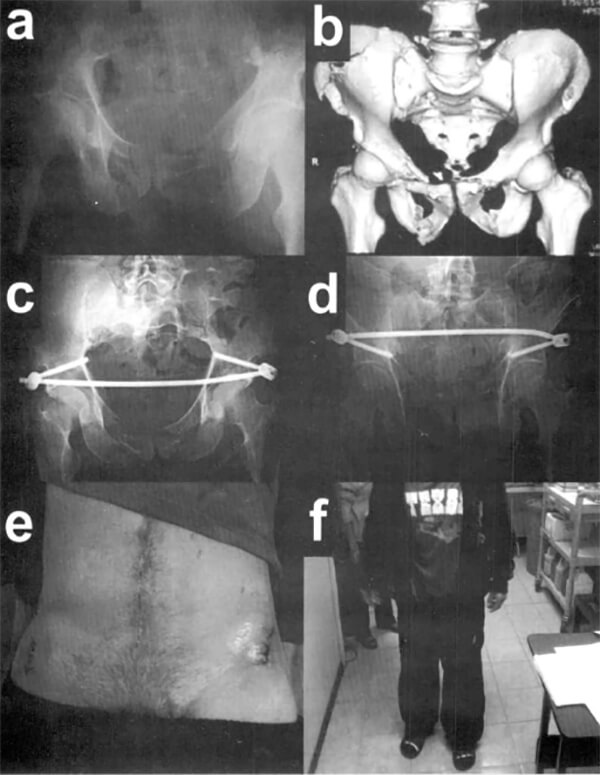

Caso 3: Radiografía anteroposterior (a) y reconstrucción 3D de tomografía computarizada (b) a su ingreso. Radiografías de pelvis en proyecciones de entrada y salida post operatorias (c y d). Fotos clínicas a las dos semanas del post operatorio, donde se evidencian las heridas operatorias a ambos lados (e) y su capacidad de soportar la carga no asistida (g y h).

Caso 1: Radiografía anteroposterior (a) y reconstrucción 3D de tomografía computarizada (b) a su ingreso. Radiografías de pelvis en proyecciones de entrada y salida post operatorias (c y d), a las 12 semanas del post operatorias (e y f), y a las 20 semanas del post operatorio (g y h).